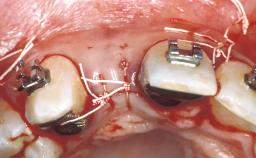

Replacement of Two Teeth in a Partially Dentate Posterior Maxilla with a Fixed Dental Prosthesis Using a Conventional Loading Protocol

In September of 1995, a 64-year-old female patient presented to our clinic with a distally shortened arch in the left maxilla and the desire for a fixed rehabilitation. The patient’s medical history did not reveal any major issues, and she did not take any significant medication. She was a non-smoker and did not report any allergies.The patient wished to restore her chewing function on the left side, which was severely compromised due to the missing teeth 25, 26, and 27. The antagonistic lower teeth were present and in acceptable condition.